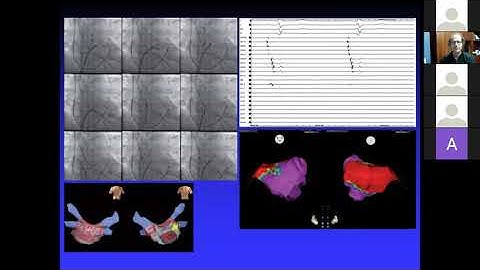

Protocol for Identifying Non PV Triggers.